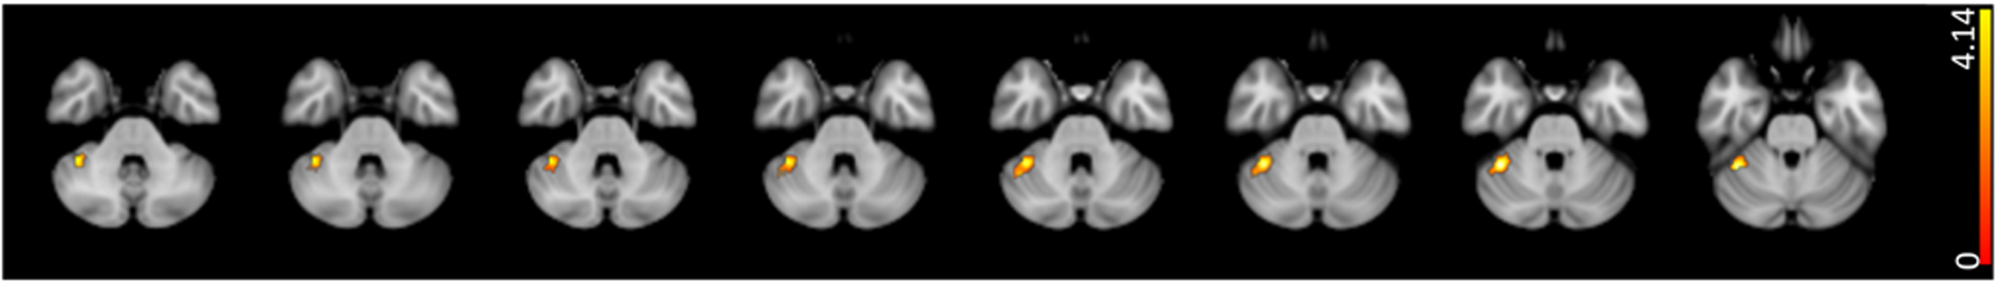

Fig. 4: Correlation of altered fastigial FC with fastigial GM volume.

The figure shows the positive correlation (red-yellow color code, p < 0.01, FDR corrected) between fastigial FC and fastigial GM volume.